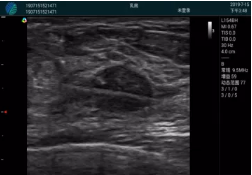

腺體內(nèi)部清晰顯示一低回聲塊影,形態(tài)不規(guī)則,邊界模糊,邊緣呈毛刺狀,內(nèi)部見(jiàn)砂礫樣鈣化

M20引導(dǎo)下穿刺活檢術(shù)